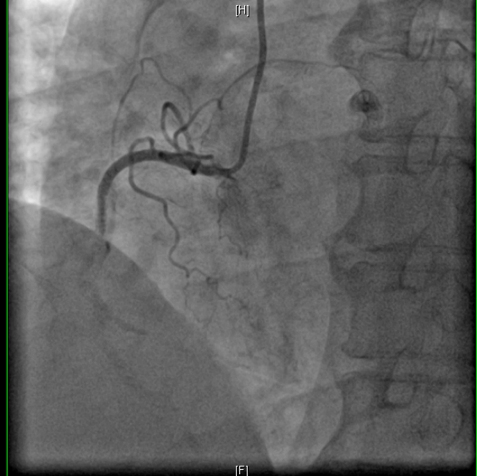

图1  RASER技术

图2 应用RASER技术治疗术前及术后的冠脉造影结果对比

准分子激光根据病变性质,选择合适的能量密度及脉冲频率,在这个病例中采用能量45mJ/mm²、频率40Hz共消蚀3次,球囊仍无法通过病变,随即换用旋磨导丝顺利通过病变并应用1.25mm磨头完成两次旋磨后,顺利完成球囊扩张及再次植入1枚支架,最终应用血管内超声(IVUS)精准评估手术后效果。